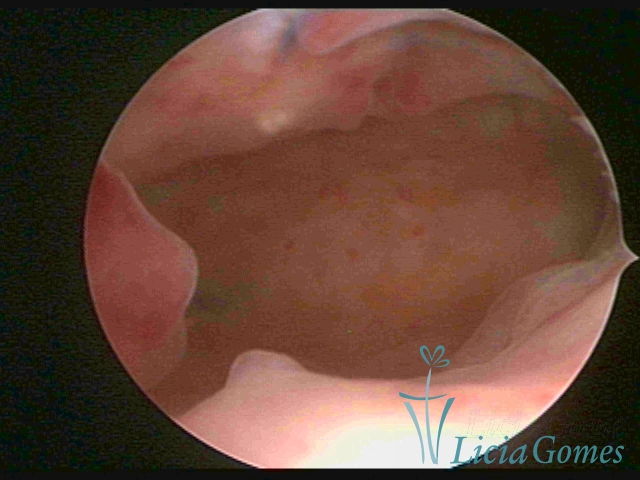

In simple hypertrophy, there is an increase in the endometrial thickness with a protuberance of the glandular punctuate, differing from the proliferative endometrial pattern by the loss of superficial reticular vascularization. Another form of simple hyperplasia is the cystic glandular hyperplasia, which also presents cystic lesions intercalated to the hypertrophic endometrium.

Complex Hyperplasia has a pseudopolypoid aspect which resembles cerebroid tissue or with decidual reaction. The superficial vascularization is more evident, presenting vessels in the shape of corkscrew or spiral.

Atypical hyperplasia and histeroscopical aspect are similar to complex hypertrophy, also presenting vascularization with atypias. With the increase of the thickness of the superficial vessels, tissues in necrosis may also be found.